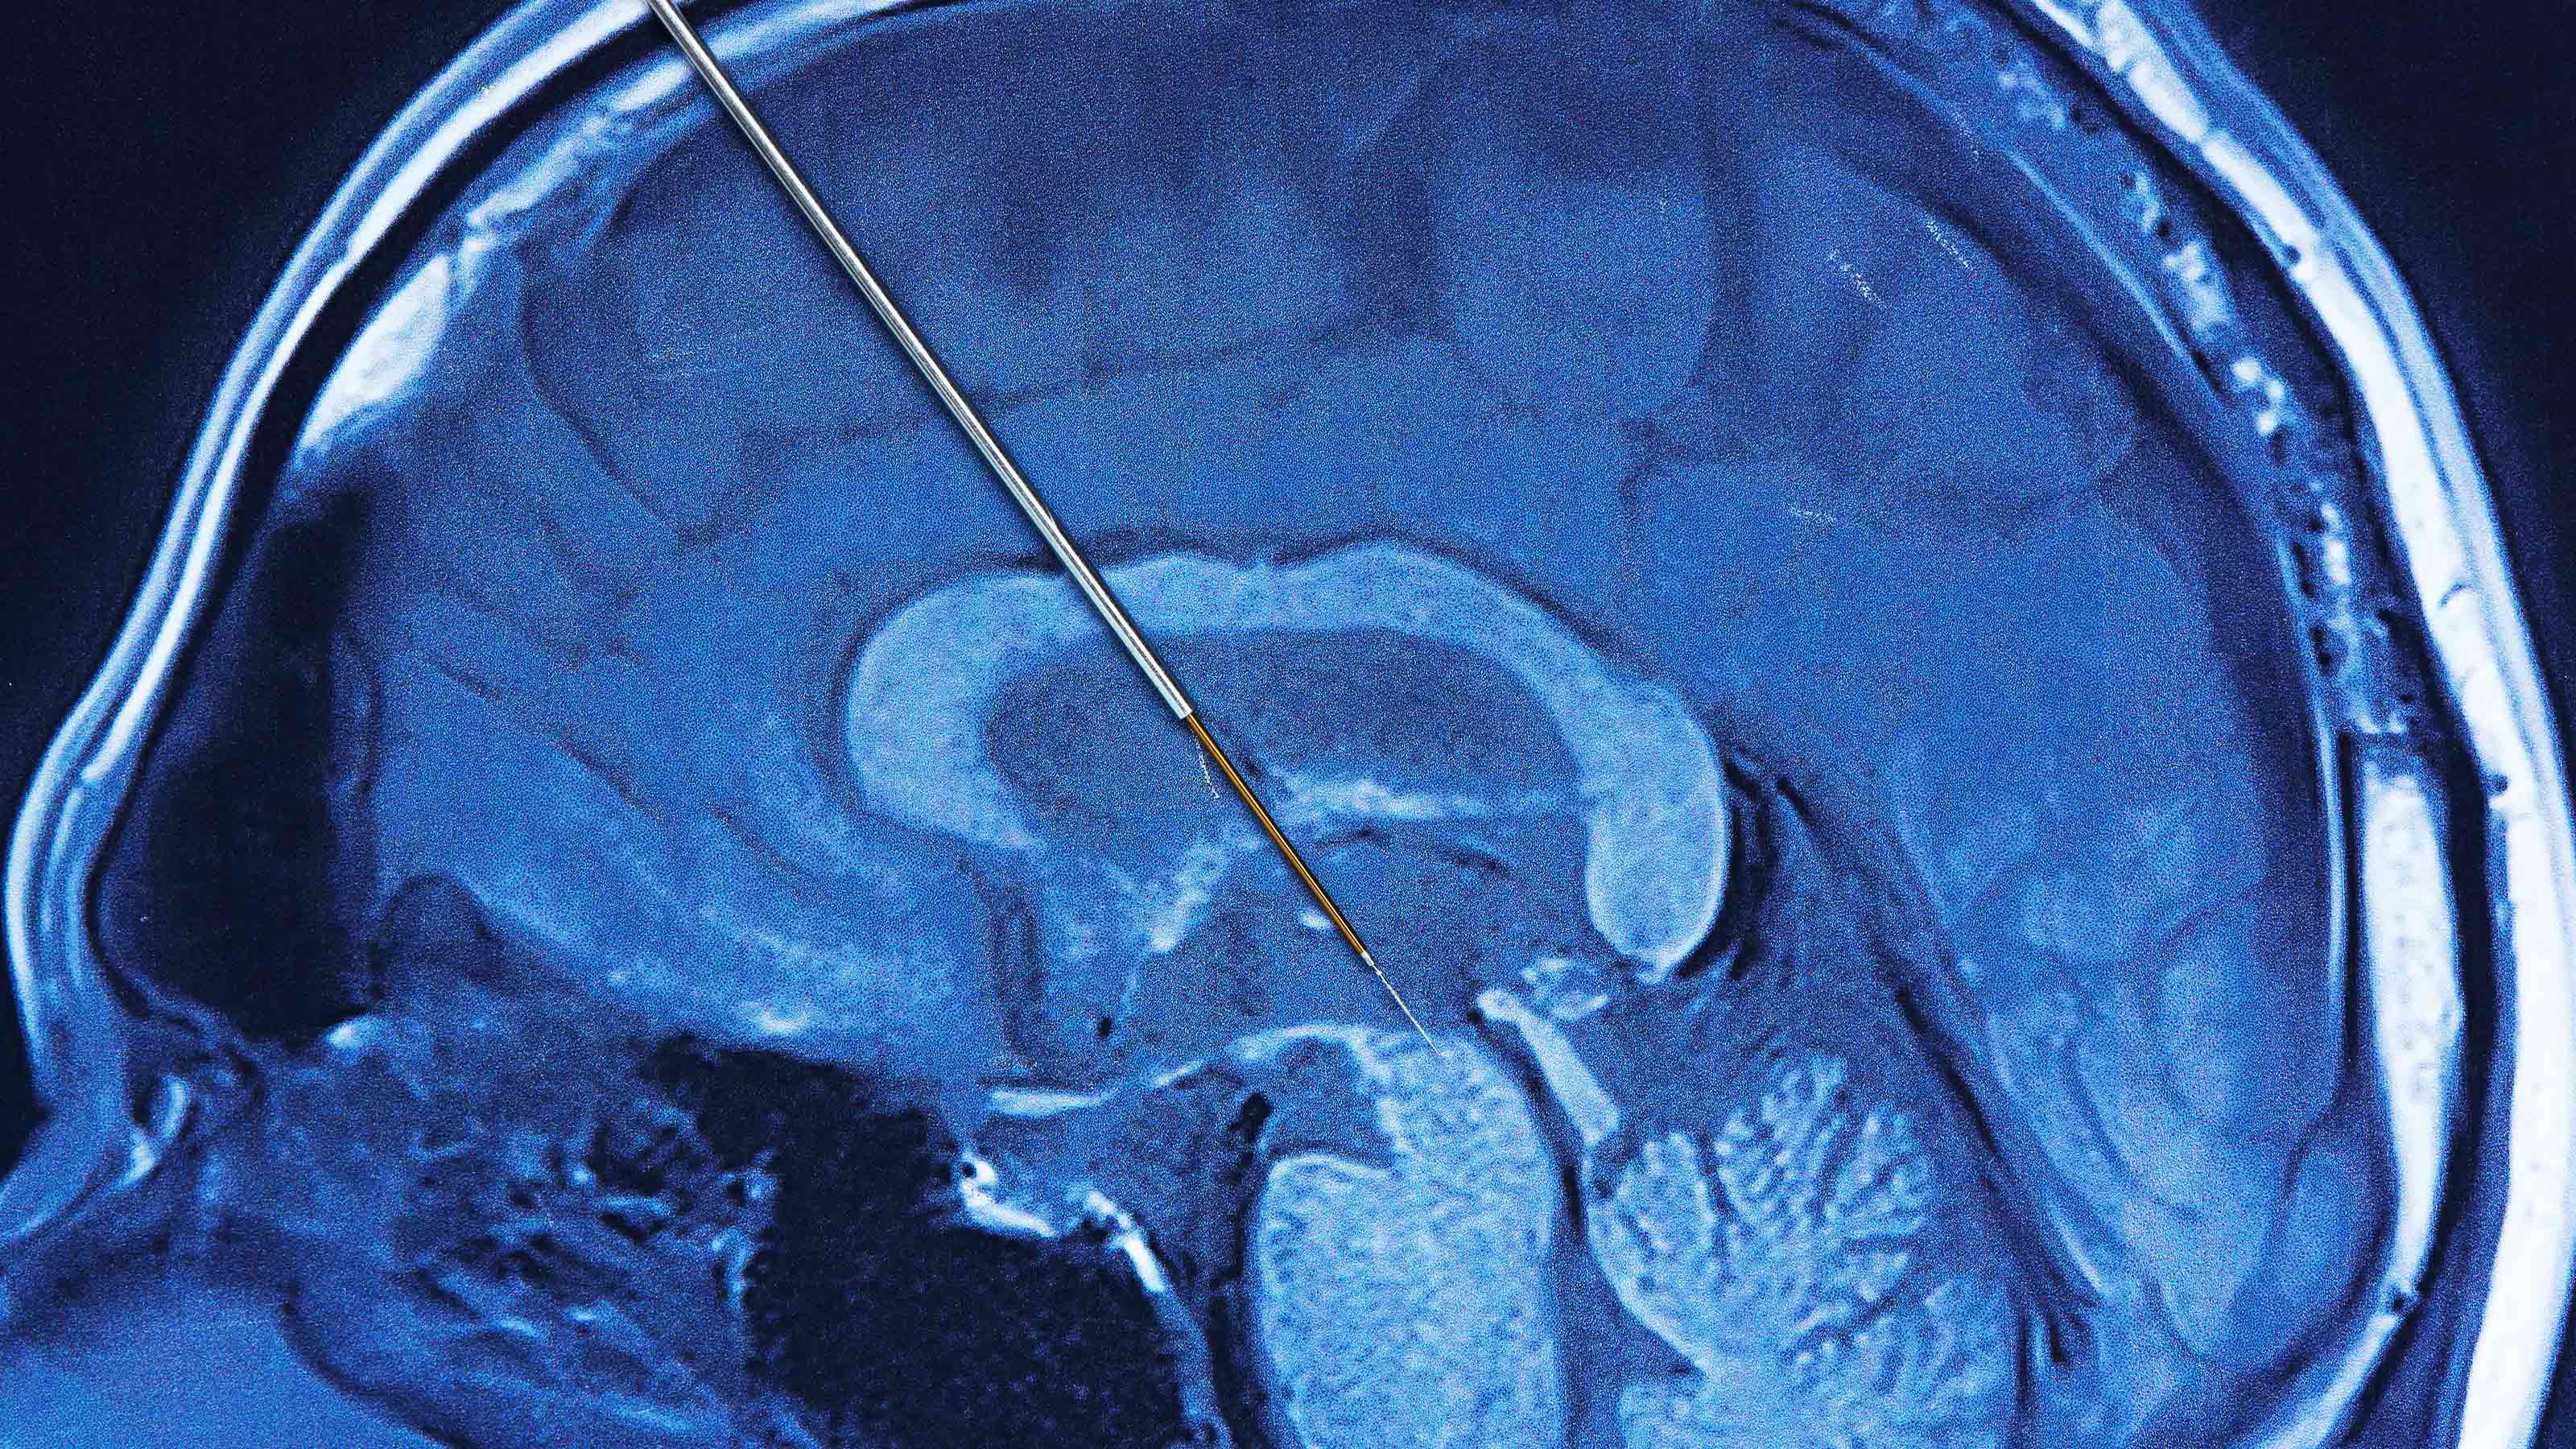

Deep brain stimulation: explained

Deep brain stimulation is being studied as a treatment for any number of neurological and psychological conditions. But what is it, exactly?